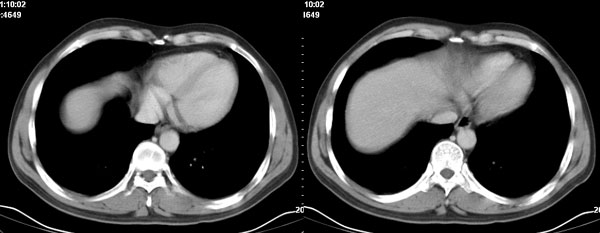

李**,男,46岁,便血1天入院,慢性贫血貌,腹平、软,剑突下压痛,肠鸣音稍活跃,hb大于1g/l,胃镜:慢性浅表性胃炎,b超:1肝内多发性占位 2腹腔内囊性肿块 ,肝内圆形影平扫ct值42.9,动脉期48.6,静脉期58.2,延迟期62.2

影像学表现:1 腹腔前中部、胰腺前方囊实性病灶(个人认为确定有否实性成分存在这是关键,涉及到鉴别诊断,如果是口服阳性造影剂则可明确左侧是不是小肠了),囊性部分囊壁不均,实性部分有强化,与小肠关系较密切,局部小肠受推移;与胰头、胃后壁均有脂肪间隙存在;2 胰腺无异常改变,胰周无渗出;3肝后段包膜下2个小圆形低密度灶,从图像和楼主提供的ct值来看有轻度强化,灶周无片状强化,不似单纯囊肿及肝癌、炎性病变表现;4 腹膜后及腹腔内无淋巴结肿大。

胰腺边界清晰,胰周筋膜不厚,胰周脂肪密度无明显增高;其前方囊实性病灶,边界清晰,增强后实性部分轻度强化;肝内多发边界清晰低密度影,增强后无明显强化(平扫ct值42.9,动脉期48.6,静脉期58.2,延迟期62.2)。

我们先确定病变来源于何处。从片上看,应该说是起源于肠道的囊实性的肿块。二、肝内低密度影,增强强化随时间强化,考虑小血管瘤。